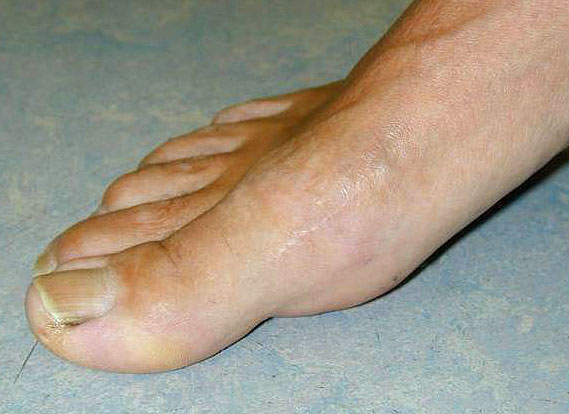

Die Röntgenaufnahmen (Abbildung 1) zeigen den Fuß einer 34 jährigen Patientin nach Exostosenabtragung. Der erhöhte intermetatarsale Winkel wurde durch eine alleinige Abtragung der Exostose nicht reduziert. Als weiterer Risikofaktor für ein Rezidiv liegt ein pathologischer Gelenkwinkel vor. Der intermetatarsale Winkel von 18 Grad kann durch eine basisnahe Osteotomie gut korrigiert werden. Da durch die gleichzeitige distale Korrektur des Gelenkflächenwinkels mithilfe einer Reverden-Green Osteotomie ein Längenverlust von ca. 2-4 mm einhergeht, bot sich als proximales Korrekturverfahren die basisnahe Open-wedge Osteotomie an, um bezüglich der Länge des Metatarsale I neutral zu bleiben (Abbildung 2). Die Kombination zweier verkürzender Verfahren (z.B. Lapidus und Reverden-Green) würden zu einem sehr kurzen ersten Strahl führen, mit dem Risiko einer Transfermetatarsalgie. Übersteigt die Verkürzung des Metatarsale I 2 mm, steigt das Risiko für die Entwicklung einer Transfermetatarsalgie deutlich an 8. Die durchgeführte Revision zeigt eine gute Stellung des 1. Strahls bei zentriert stehendem Gelenk.